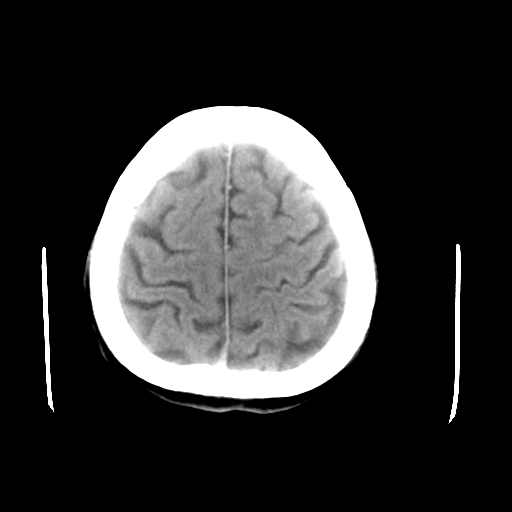

以下是引用liuyue在2008-4-28 13:34:00的发言:[br]右额叶条状高密度影,边缘清楚,周围未见水肿及占位.[br]考虑:血管畸形可能性大.[br]建议:强化ct扫描或mri检查.除外脑回钙化.

以下是引用论黑辩白在2008-4-28 12:53:00的发言:[br]右额叶局限性脑萎缩,右额叶见条状高密度影,建议mri进一步检查。[br][br][本贴已被 论黑辩白 于 2008-4-28 13:08:16 修改过]